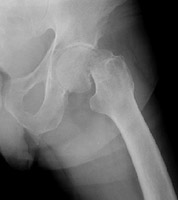

- Click on the image for a larger versionELateral radiograph of the left hip. This demonstrates a Garden IV fracture of the femur.

- Click on the image for a larger versionFAP radiograph of the left hip. This again shows the Garden IV fracture of the left femur.